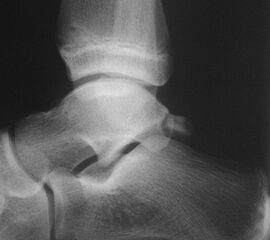

Fugengelenkfrakturen treten typischerweise vor dem 10. Lebensjahr auf, in einer Phase, in welcher die Wachstumsfugen noch weit offen sind. Dieser Frakturtyp betrifft fast ausschließlich den medialen Malleolus. Laterale Frakturen sind extrem selten, teilweise kommt es zu lateralen Bandverletzungen oder Fugenschaftfrakturen der distalen Fibula. Die Frakturlinie verläuft in einer Verlängerungslinie von der medialen Taluskante nach proximal. Häufig stellen sich Verletzungen des Innenknöchels im Röntgenbild schlechter dar, insbesondere wenn die Aufnahmen verdreht sind oder die Ebene der Fraktur bei geringer Dislokation verkippt zur Röntgenebene liegt. Besteht klinisch der geringste Hinweis auf eine Verletzung des Innenknöchels, muss aufgrund der Tragweite der Verletzung durch entsprechende Aufnahmen gegebenenfalls auch Schnittbildverfahren die Verletzung sicher diagnostiziert oder ausgeschlossen werden (Abb. 15).

Fugengelenkfrakturen können die Wachstumsfuge durchkreuzen (Abbildung 16a), ohne oder nur mit minimaler Beteiligung der Fuge sehr weit medial liegen (Abbildung 16b) oder durch die Fuge auslaufen (Abbildung 16c). Relevant für die Wachstumsprognose ist weniger die Form der Fraktur, sondern das Alter des Patienten zum Zeitpunkt des Traumas sowie das Ausmaß der Schädigung der Wachstumsfuge, wobei eine Korrelation mit dem Ausmaß der Dislokation besteht.